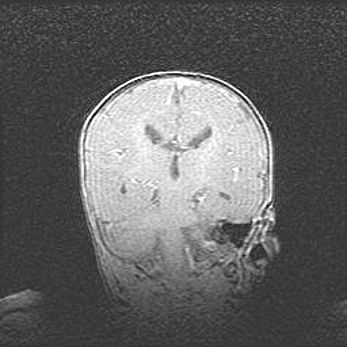

Церебральная ишемия II.

Возраст: 7 дней

Вес: 3350 г

Пол: женский

Окружность головы: 35 см

Срок гестации: 39 недель

Ишемия головного мозга – это состояние, которое развивается в ответ на кислородное голодание вследствие недостаточного мозгового кровообращения. У новорожденных она является следствием дефицита кислорода, что ведет к метаболическим расстройствам различной степени тяжести в тканях головного мозга, в том числе к развитию коагуляционных некрозов и гибели нейронов.